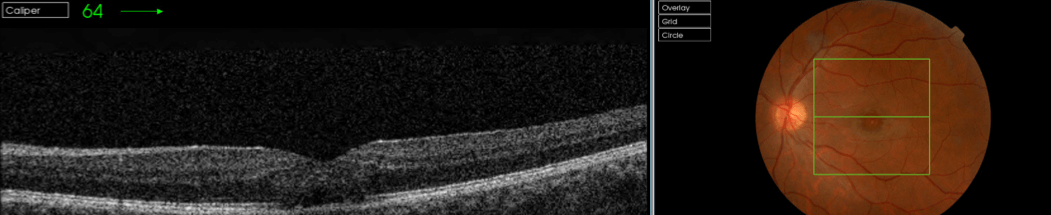

Actualmente podemos caracterizar las lesiones mediante las pruebas de imagen que aportan valoración cuantitativa y cualitativa. Es interesante, adicionalmente a la exploración funduscópica estudiar las lesiones mediante retinografía, OCT, angio-OCT, autofluorescencia, microperimetría y oftalmoscopía láser confocal(SLO). Todas ellas aportan información complementaria en el estudio, diagnóstico y seguimiento de las lesiones. A continuación se muestran retinografías y OCTs de un caso de retinopatía solar y un agujero macular producido por la acción de un láser en una discoteca ( Figuras 1,2,3,4)

La tomografía de coherencia óptica (OCT

) muestra un espacio hiporreflectivo característico en la retina externa en pacientes con retinopatía solar crónica. Los hallazgos son congruentes con la histopatología de esta condición y constituyen una herramienta clínica útil para confirmar el diagnóstico. 8,11

Figuras 1 y 2. Retinopatía solar bilateral crónica en paciente varón, ocurrida en el año 1970 mirando un eclipse solar, en el momento de la lesión el paciente tenía 38 años, agudeza OD:07 NMA, agudeza OI: 0.5, NMAE ( no mejora con agujero estenopeico).

Figuras 3 y 4. Agujero macular monocular producida por la acción de un láser en una discoteca en varón de 27 años, agudeza visual en el ojo afecto de 0.1.